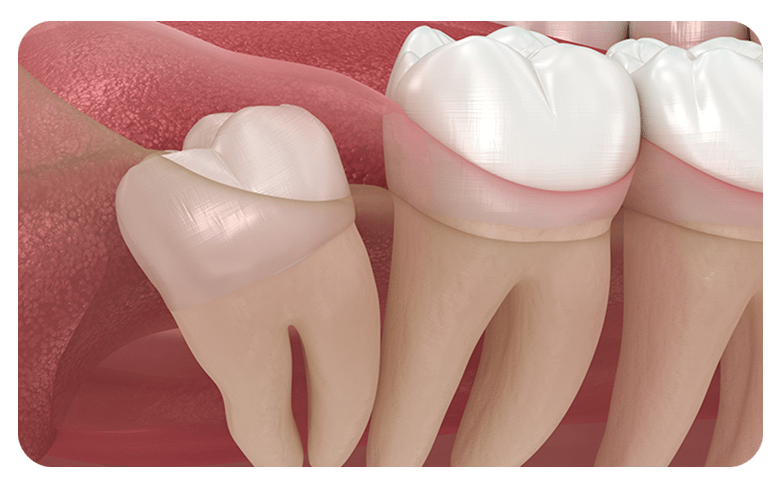

매복사랑니란?

사랑니가 완전히 맹출 되지 않고 잇몸 아래 묻혀있는

형태의 사랑니를  매복 사랑니라고 합니다.

사랑니가 완전히 맹출 되지 않고 잇몸 아래에 묻혀있는 형태의 사랑니를 매복 사랑니라고 합니다.

매복 사랑니는 함치성낭종, 염증 유발, 턱뼈 손상 등의 문제를 유발할 수 있어 발치해주는 것이 좋습니다.

부분매복

수직매복

원심경사 매복

수평매복

사랑니는 신경관, 상악동 등과 가깝게 맞닿아 있어

잘못 발치할 경우 상악동천공, 감각이상,

신경 손상 등의 부작용이 발생할 수 있습니다.

잘못 발치할 경우 상악동천공, 감각이상, 신경 손상 등의 부작용이 발생할 수 있습니다.